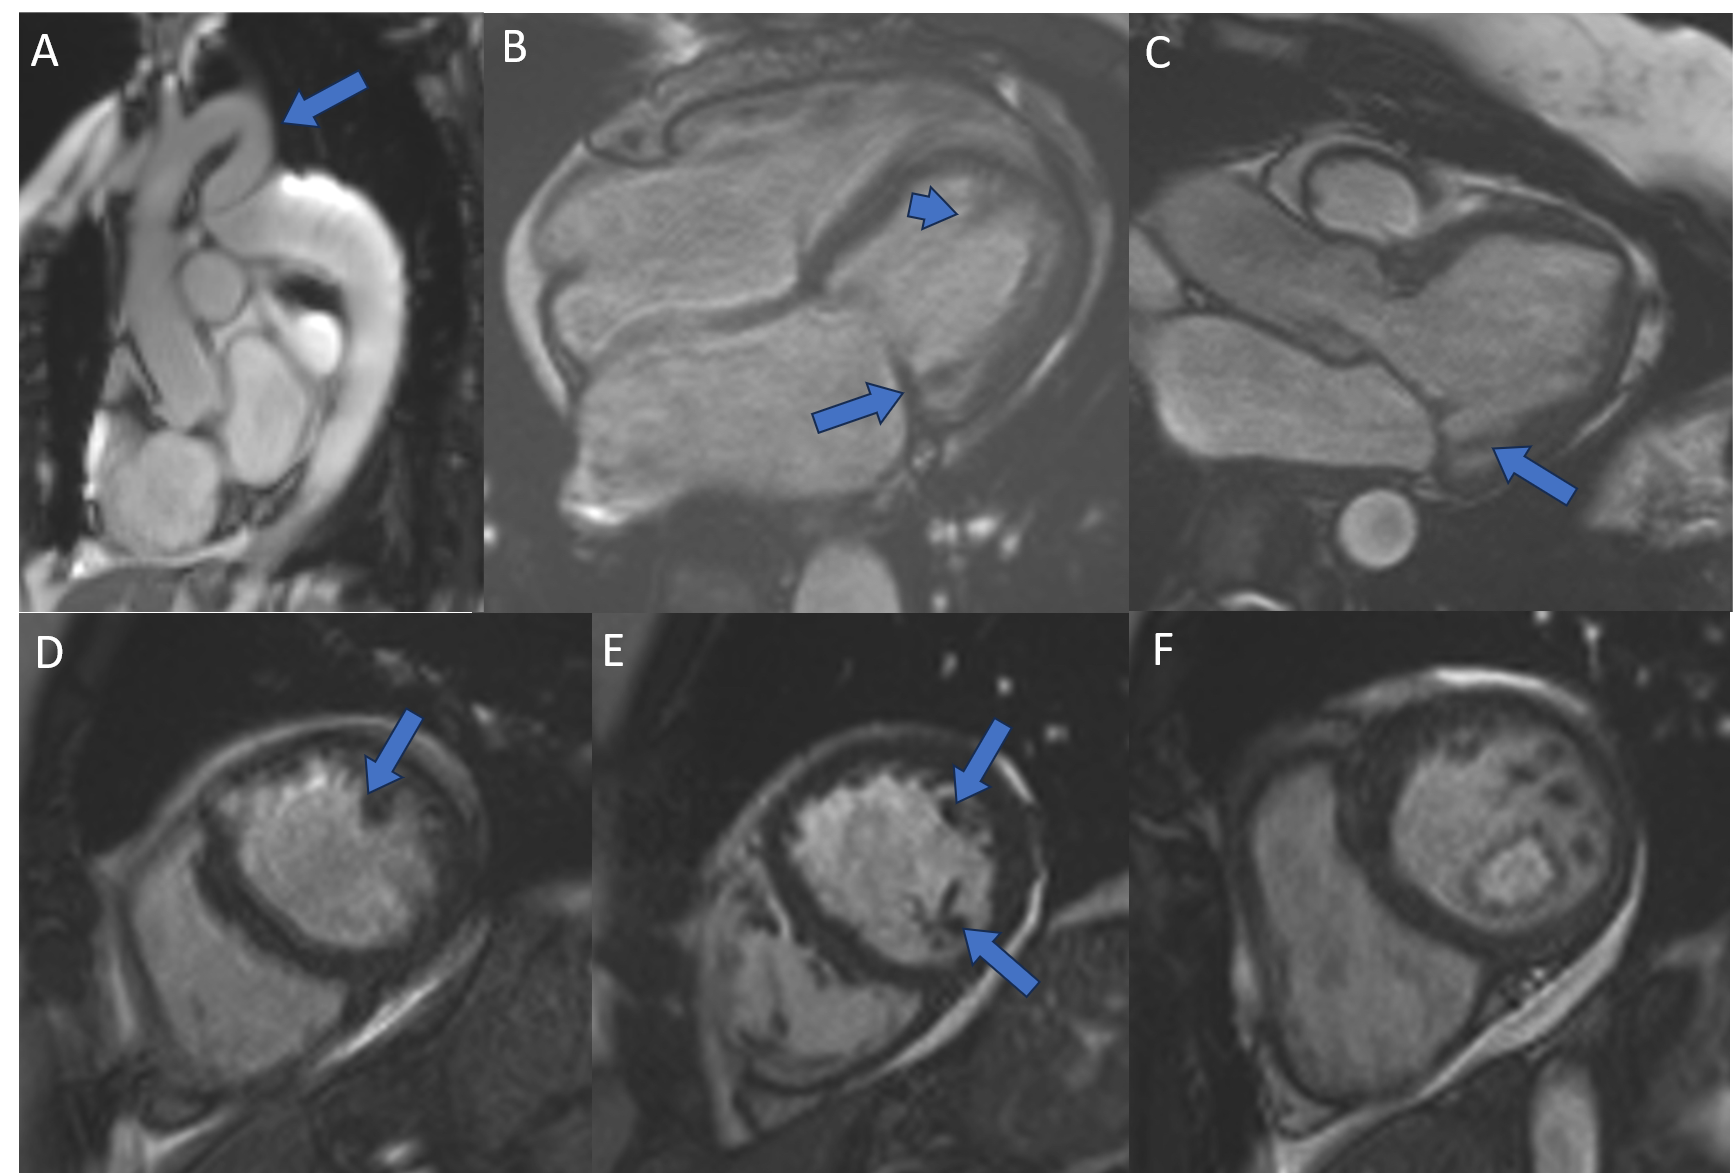

Fig. 2: 4D flow of aortic coarctation with flow acceleration in stenosis and turbulent flow in post stenotic dilatation.